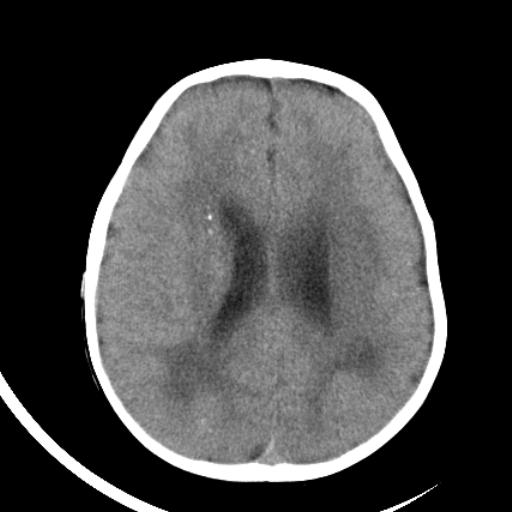

双侧脑室前后角周围白质片状低密度影,双侧侧脑室旁、双顶叶皮层及皮层下多个小原点状钙化灶,不除外torch感染。右顶叶脑回似乎较对侧大,建议mri检查以除外脑发育异常。

考虑:1、巨脑回畸形(皮质明显增厚+脑回明显增宽+白质减少)。

2、torch综合征(室管膜下钙化+白质内及皮髓质交界处多发钙化)。